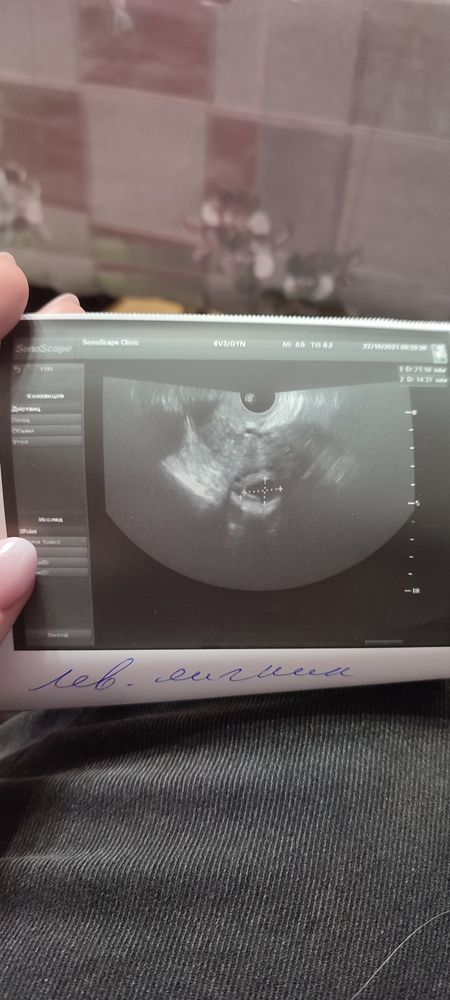

Была на контрольном УЗИ сегодня, овитрель кололи 20.10 22.00

Врач сказал, что фолликул деформировался, есть немного позади маточной жидкости, но сказал что видит ооцит, и я вот не поняла, это получается, что овуляция случилась? Или вот-вот??

Это был момент овуляции, из яйценосного бугорка уже истекала жидкость и вот вот должна была выйти ЯК, если б минут на 5-15 позже посмотрели, то она бы уже вышла и бугорок исчез бы. ЖТ появится буквально завтра-послезавтра на месте этого ДФ. Ну пока сосудиками обрастет, пока лютеин накопит. В общем, ваша ЯК уже в трубе ждёт встречи с женихом, у вас 12-20 часов на это)